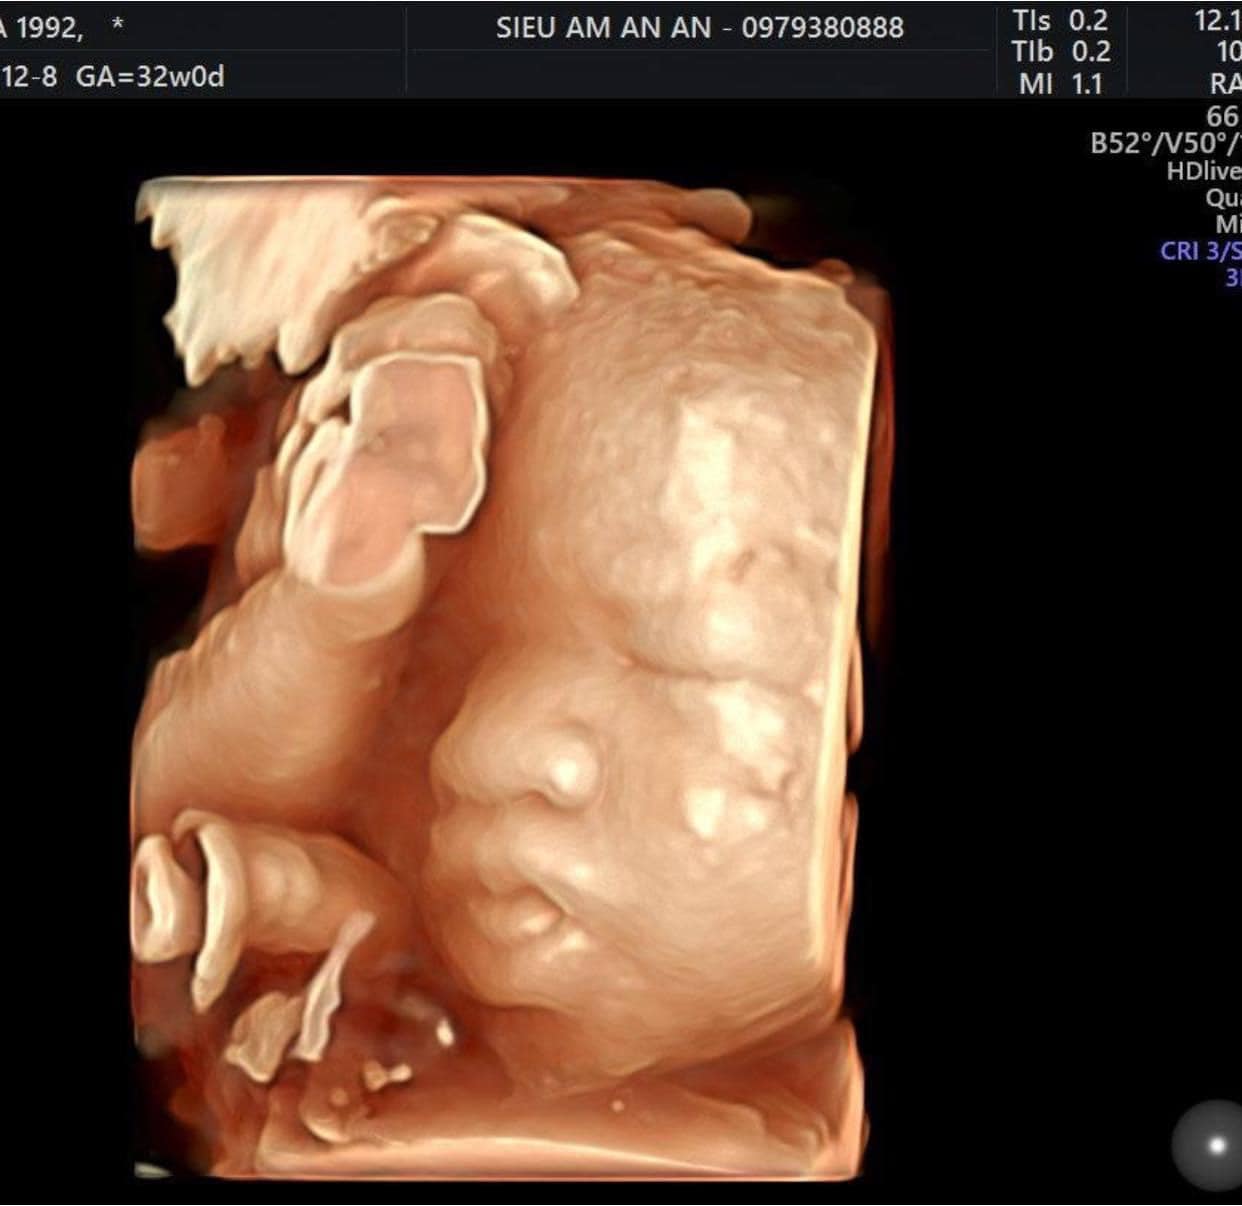

Siêu âm có thể thấy một chút tóc trên đầu bé.

Siêu âm thai nhi để tầm soát dị tật lần cuối.